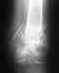

Почти два года назад сломала левое предплечье, была проведена операция - установили металлоконструкцию (пластины и спицу). Летом этого года все сняла. После снятия рентген не делали, через месяц рука начала болеть и опухать. Сделала снимок, в Москве была на консультации, где сне сказали, что у меня ничего не срослось и уже образовался ложный сустав (необходима операция, т.е. снова ставить пластины или аппарат Илизарова). Рукой почти ничего не могу делать. Посоветовали обратиться к вам, подскажите, могу ли я сделать у вас операцию по удалению этого ложного сустава и установке металлоконструкций. Нужно для обращения к вам направление и если такие операция платно, то сколько примерно это будет строить. Заранее очень Вам благодарна за ответ. Хотелось бы прооперировать руку именно у Вас.